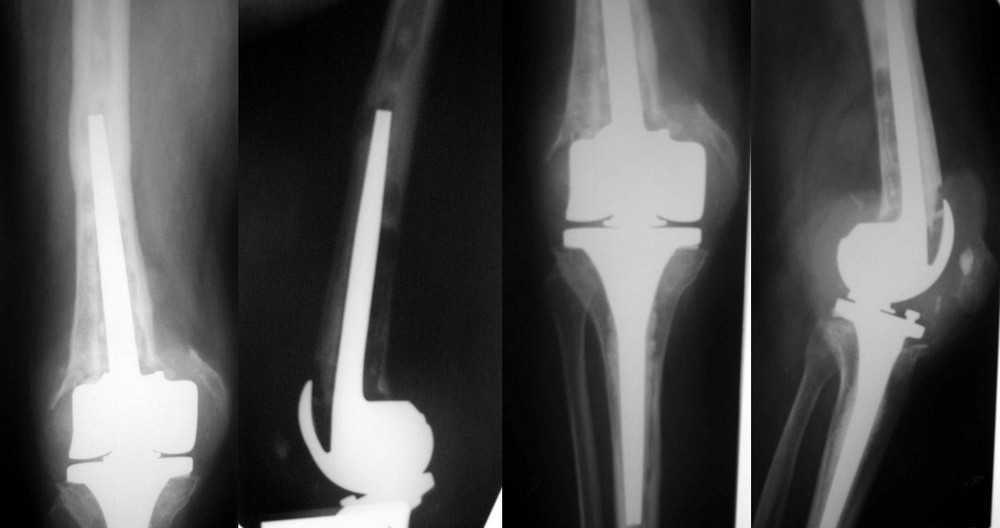

Пациентка 72 лет. Асептическая нестабильность бедренного компонента ротационного

протеза Endo-Model (Waldemar Link).

Тибиальный компонент наиболее вероятно стабилен по

данным R-графии. Индивидуальный эндопротез у W.Link оказался неподъемным по цене.